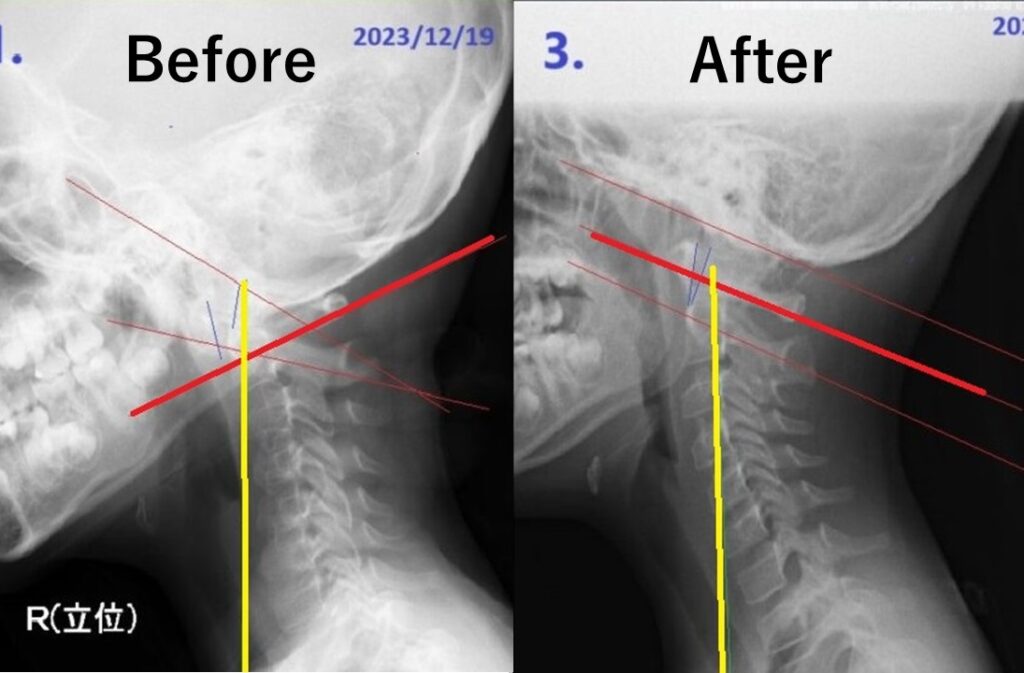

9歳女児の例

施術後、頭蓋骨と第一頚椎(アトラス)・第二頚椎(アキシス)は正常な位置を取り戻します。重心が正しく変化することで頚椎の正しい骨組みを実現し、症状を解消しています。